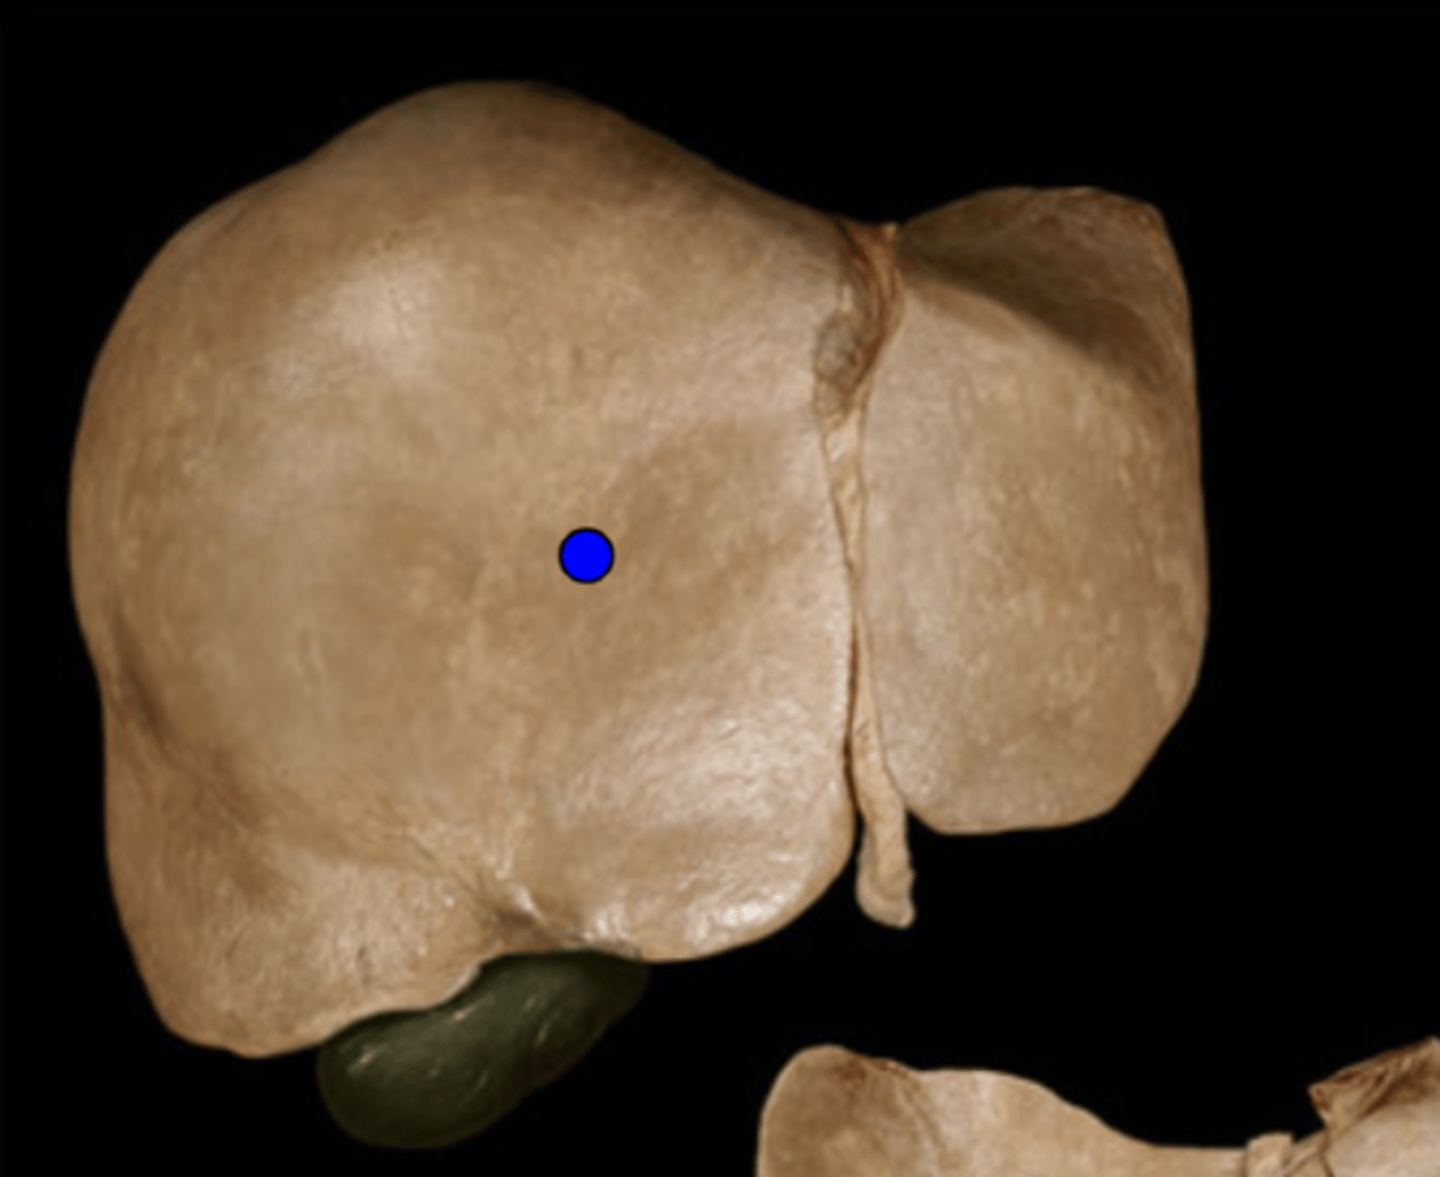

Right Lobe of Liver

Left Lobe of Liver

Caudate Lobe of Liver

Quadrate Lobe of Liver

Falciform Ligament

Ligamentum Teres

Gall Bladder